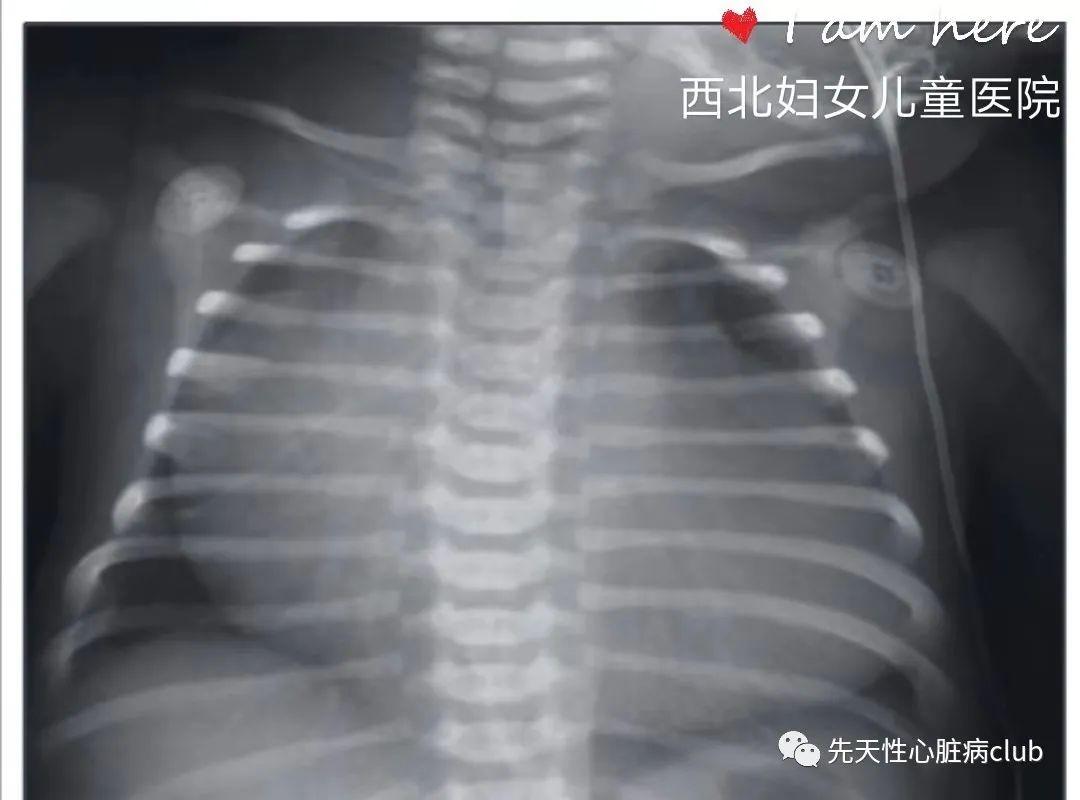

图2:PA/IVS胸部x线